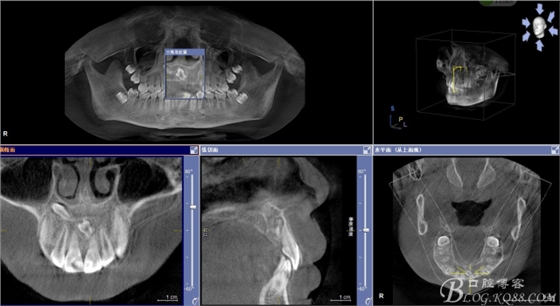

患者、男、15歲,主訴:牙齒不整齊,要求正畸治療。專科檢查:見圖1 ,cbct檢查:11與21之間,12與13之間各有異倒置多生牙,尤其以21根尖區(qū)多生牙位置高,與患者家屬充分溝通,患者同意拔除兩顆多生牙。簽知情同意書。

圖2.cbct影像檢查:11與21之間有一倒置多生牙。

圖3.cbct影像檢查:12與13根尖上方也有一顆倒置多生牙,接近鼻底。